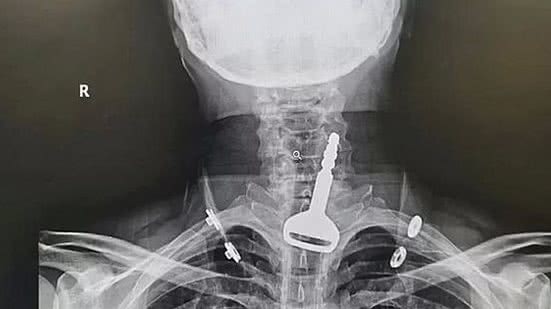

Ele foi levado às pressas a um pronto-socorro da região com quadro de asfixia e uma radiografia revelou o local exato onde a chave ficou retida.

O homem, que é paciente cardíaco, enfrentou uma cirurgia endoscópica de 15 minutos para a retirada do objeto e permanece no hospital, em observação.